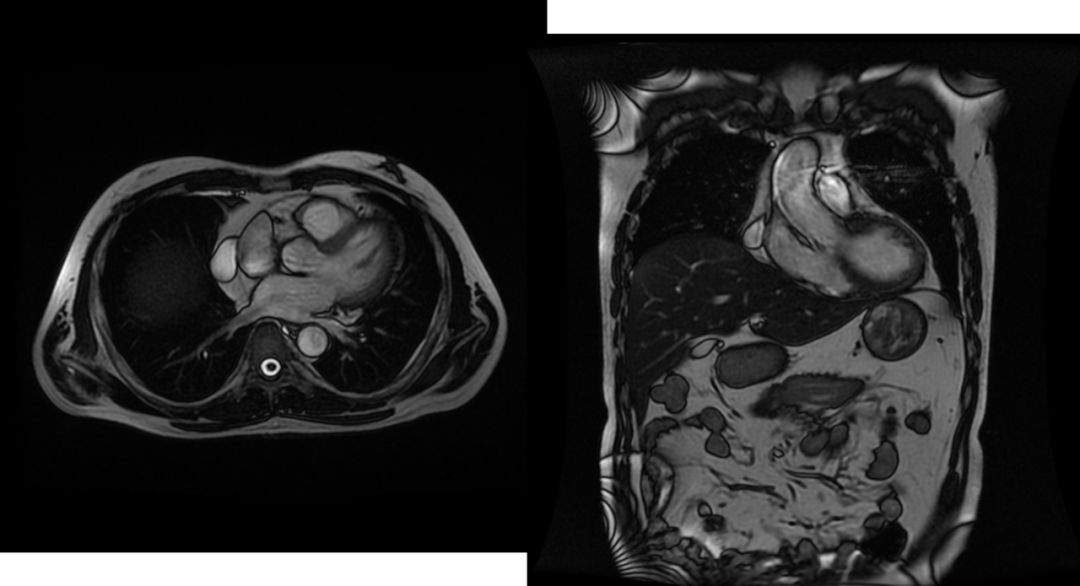

5.后纵隔肿瘤

神经源性肿瘤为后纵隔肿瘤中最常见者。

部位:好发于后上纵隔,侧位片上与脊柱重叠;

形状:多为圆形或椭圆形;

边缘:清楚锐利;

密度:均匀略低。

发生于椎间孔者,可压迫椎间孔使之扩大,并可压迫肋骨头及脊椎,产生边缘光滑的压迹,肿块呈哑铃状,一端在椎管内,另一端在纵隔内。可以产生神经压迫症状。恶性肿瘤呈分叶状,侵蚀邻近骨骼而发生破坏;神经母细胞瘤内可发生钙化;中度强化。

后纵隔肿瘤影像学表现